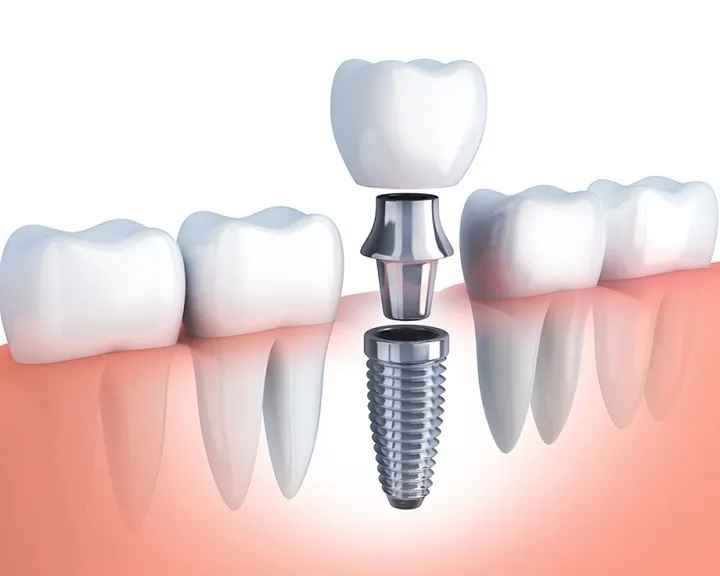

Răng sứ lõi Titan có cấu tạo gồm hai phần:

- Khung sườn kim loại bên trong: Được làm từ hợp kim Niken-Crom-Titan, trong đó Titan chiếm khoảng 3-6%. Nhờ vậy, khung sườn rất nhẹ, cứng chắc và có khả năng chống ăn mòn cao.

- Lớp men sứ bên ngoài: Là lớp men Ceramco III. Được phủ chồng nhiều lớp mỏng trên bề mặt. Nó giúp tái tạo hình dáng và màu sắc rất tự nhiên, gần giống với răng thật.

Với những đặc điểm này, răng sứ lõi Titan mang lại độ bền cao, đảm bảo thẩm mỹ. Đồng thời loại răng này có hiệu quả lâu dài trong các giải pháp phục hình răng.